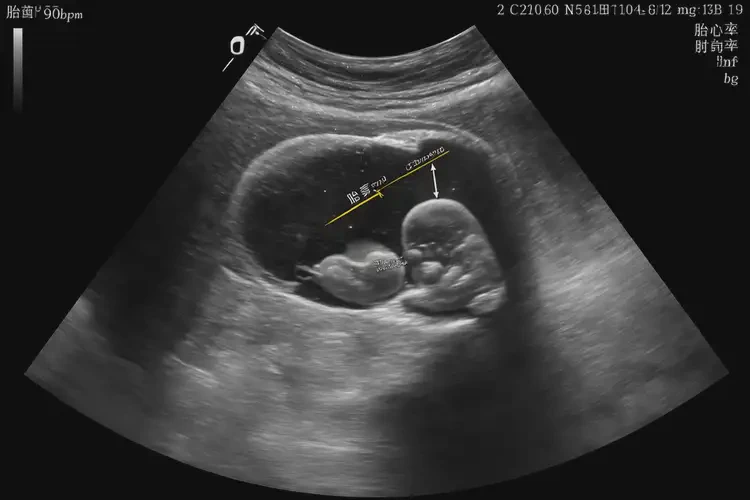

懷孕20多天胎心90左右正常嗎

懷孕20多天時,胎心率在90次/分鐘左右可能偏低,但需要結(jié)合具體情況來判斷是否正常。以下是一些相關(guān)因素和建議:

1. 早期胎心率:在懷孕6-8周時,胎心率通常在100-180次/分鐘之間。

2. 胎心率變化:胎心率會隨著孕周的增加而逐漸下降,到懷孕12周左右會穩(wěn)定在120-160次/分鐘之間。